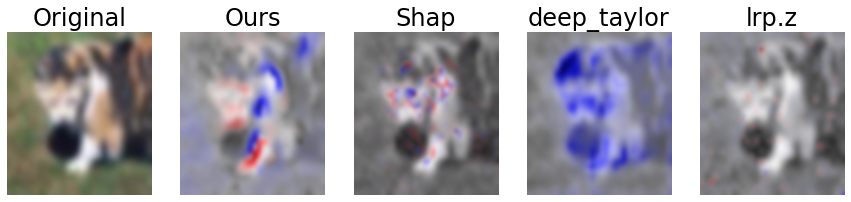

The results of the user study are listed in Tables 3 through 6 and visualized exemplarily for the LIDC-IDRI data set in Fig. 11. A qualitative comparison of our approach to DeepSHAP, DeepTaylor and LRP is depicted in Fig. 8.

CIFAR-10

On the cats-vs.-dogs dataset, DeepTaylor was clearly superior to the other tested methods with average z-adjusted values of 2.07, 2.29 and 0.90 for intuitive validity, semantic meaningfulness and image quality. Our method ranked second with average values of 0.82, 0.85 and 0.08, exhibiting significantly better ratings than LRP regarding intuitive validity and semantic meaningfulness (, ). The differences to DeepTaylor were not significant with and . While the inter-observer reliability for intuitive validity and semantic meaningfulness was moderate with to , it was low for the image quality criterion with only , basically forming two clusters where one preferred parsimonious and the other fully colored annotations (cf. Sec. 4.3). The was .646 with the largest prinicipal component accounting for 76.6 % of the variance. This pattern mostly repeated for the trucks-vs.-cars dataset with average z-adjusted values for intuitive validity, semantic meaningfulness and image quality of 2.58, 2.76 and 2.03 for DeepTaylor, and 1.10, 1.55 and 0.77 for our method. While our method achieved significantly higher values than DeepSHAP and LRP for intuitive validity and semantic meaningfulness, no significant differences were observed for image quality. Similarly, the differences to DeepTaylor were not significant with . The inter-observer reliability was for intuitive validity, semantic meaningfulness and image quality, respectively, showing a similar pattern as for the cats-vs.-dogs dataset. The was .736 and the largest principal component explained 88.0 % of the variance.